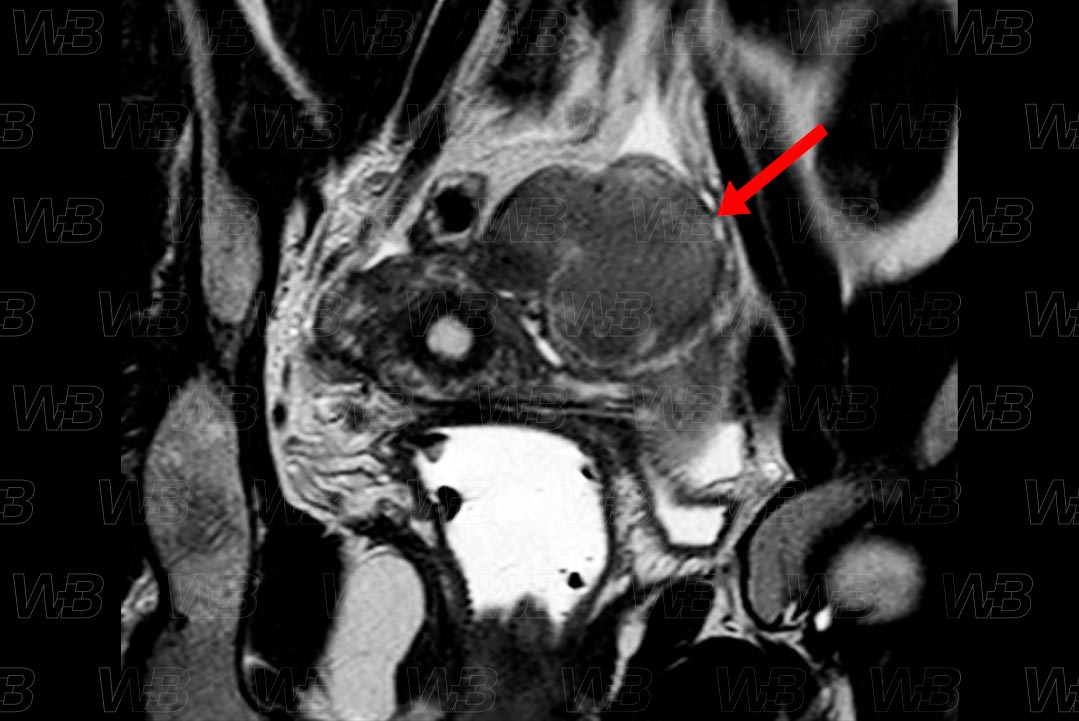

Texto alternativo para a imagem Figura 2. Crédito: Dra. Elazir Mota - Rio de Janeiro/RJ

Descrição da lesão: Ressonância magnética da pelve feminina, estudo coronal (figura 1) e axial (figura 2) em T2, evidenciando volumoso endometrioma no ovário esquerdo, bastante hipointenso em T2, configurando shading .

• Ressonância magnética da pelve: P rincipal exame de imagem a ser solicitado, diante da suspeita clínica. O protocolo utilizado deve incluir estudo T1 no plano axial e sagital. Realizar um pulso de saturação de gordura, deve ser acrescentado para auxiliar na identificação de focos endometriais com conteúdo hemático. O sinal na sequência T2 é variável. O gadolínio não acrescenta grandes informações. Vale destacar que os endometriomas geralmente, surgem como lesões hiperintensas em T1 e predominantemente, hipointensas nas imagens em T2 (aspecto denominado em sombra - shading ).